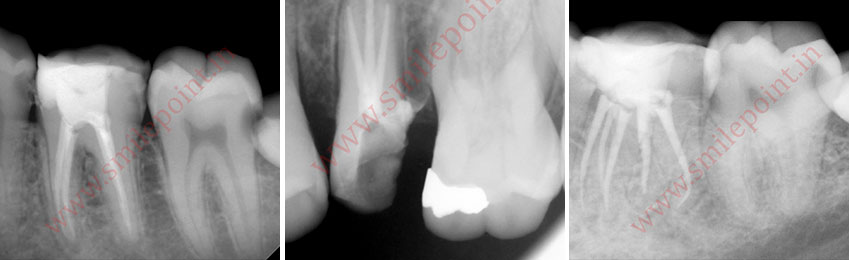

Computer Assisted Root Canal Treatment